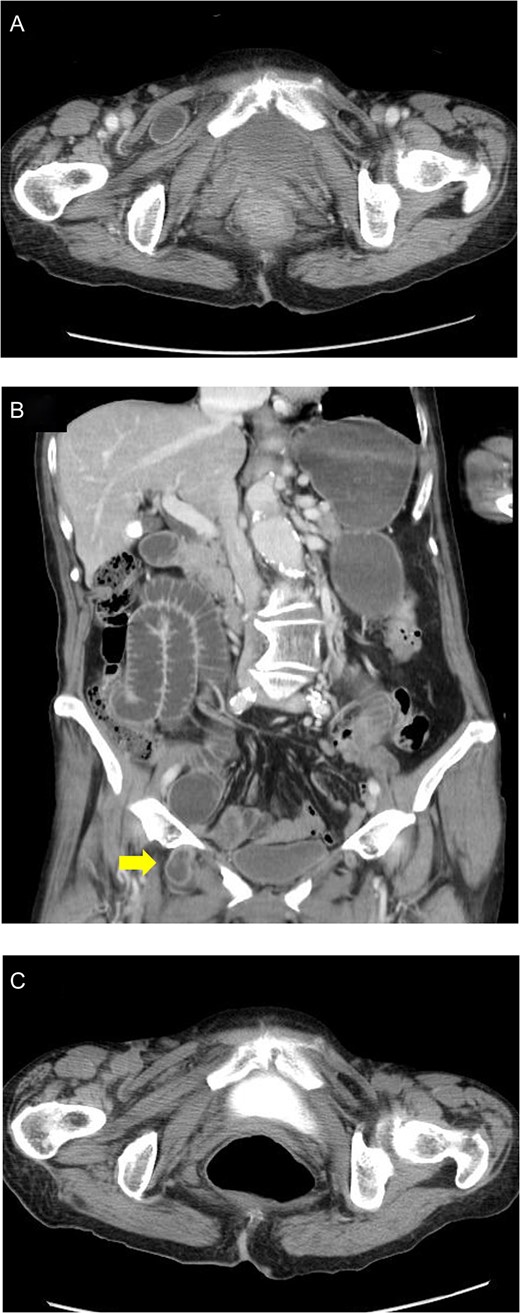

A computed tomography (CT) image revealed an incarcerated obturator hernia on the right side (Fig. 1A) and the oral side intestine was markedly distended. The bowel wall of the incarcerated intestine showed contrast enhancement but did not show irreversible ischaemic change or perforation (Fig. 1B). We did not detect obturator hernia on the left side (Figs 1A and 1B). We then successfully reduced the incarcerated intestine by using an echocardiography probe. After reduction (Fig. 1C), her abdominal symptoms improved. On the seventh day following admission under heparin displacement, we performed laparoscopic transabdominal peritoneal repair of the obturator hernia. After confirming the obturator hernia on the right side, we cut the peritoneum on the Cooper ligament, and the preperitoneal space around the obturator foramen was dissected (Fig. 2A and B). A prosthetic mesh (6 × 7 cm in size) was then inserted into the dissected space (Fig. 2C). Tacking the mesh onto the Cooper ligament, the obturator foramen was covered by the mesh maintaining a 2–3 cm margin, and the peritoneum was closed with sutures (Fig. 2D). During laparoscopy, an occult obturator hernia on the left side was detected. Subsequently, the left side obturator hernia was repaired by the same method (Fig. 3A–D). A continuous intravenous infusion of heparin and oral warfarin was started on the first postoperative day. The patient was discharged on the seventh postoperative day with an uneventful postoperative course.

(A) Incarcerated obturator hernia on the right side was confirmed by CT image. Bowel wall of the incarcerated intestine showed contrast enhancement without findings of irreversible ischaemic change or perforation. (B) Coronal plane of CT image, before reduction. The oral side intestine was markedly distended and contrast enhanced. (C) Reduction of the incarcerated intestine was confirmed by CT image.